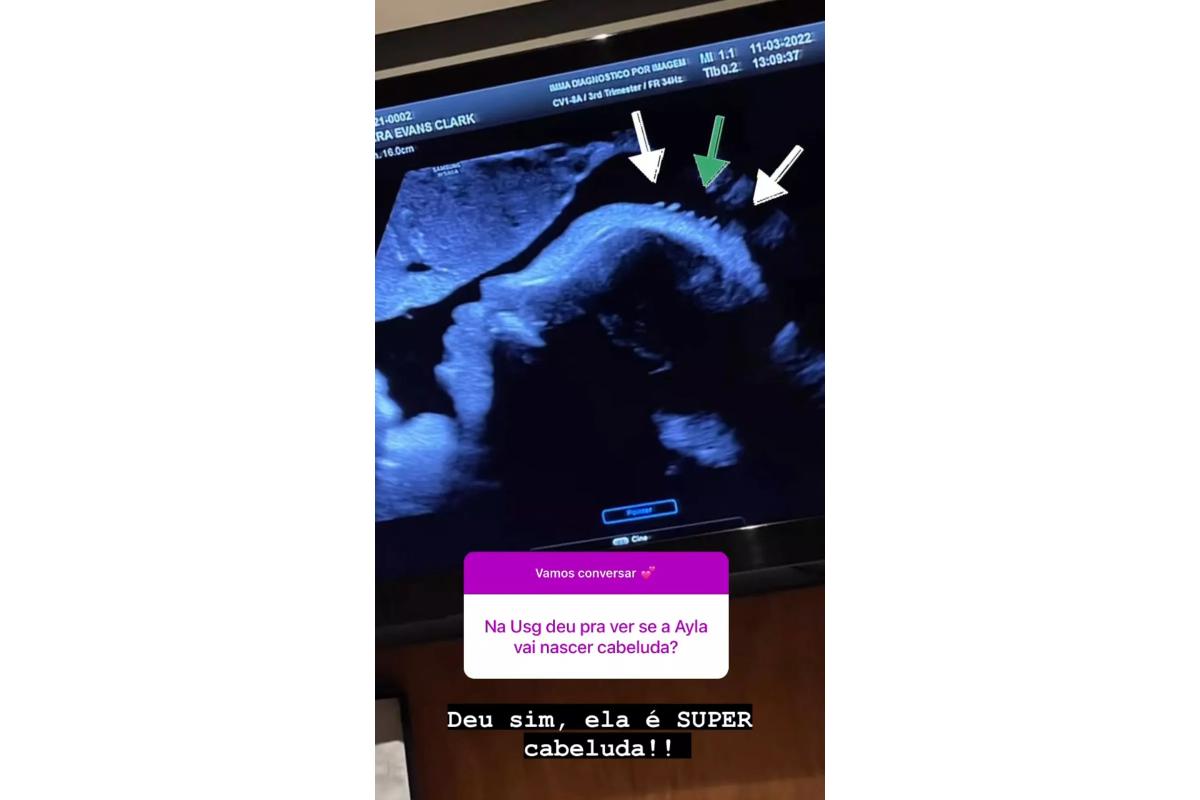

Bárbara Evans usou as redes sociais neste sábado, 26 de março, para compartilhar o ultrassom registrado durante sua última visita ao médico.

Ela está à espera da primeira filha, Ayla, fruto do relacionamento com Gustavo Teodoro. Nos stories do Instagram, a modelo contou que a bebê está atualmente com 50cm e 2,9kg.

Bárbara ainda mostrou que a filha já tem bastante cabelo. “Ela é cabeluda”, entregou a influenciadora ao postar outra imagem com detalhes.